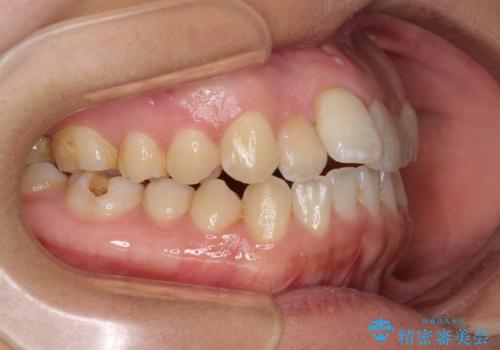

- 上下のデコボコを改善したいとのことで来院された患者様です。

近々妊娠する予定であり、極力短期間で治療したいとのことで、ワイヤー装置による非抜歯矯正治療を行うこととしました。